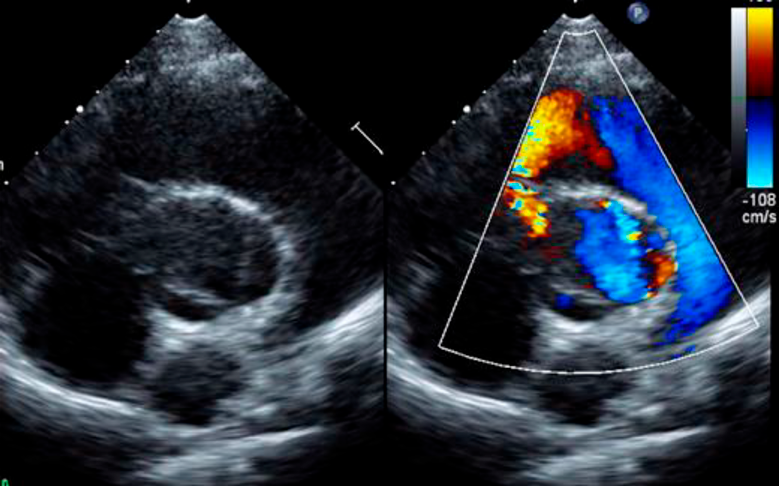

大動脈縮窄術後再狭窄および大動脈弁閉鎖不全症に対して側開胸を併施した正中アプローチによる再手術の1例Combined Full Median Sternotomy with Left Thoracotomy Approach for Recoarctation of the Aorta Associated with Aortic Regurgitation